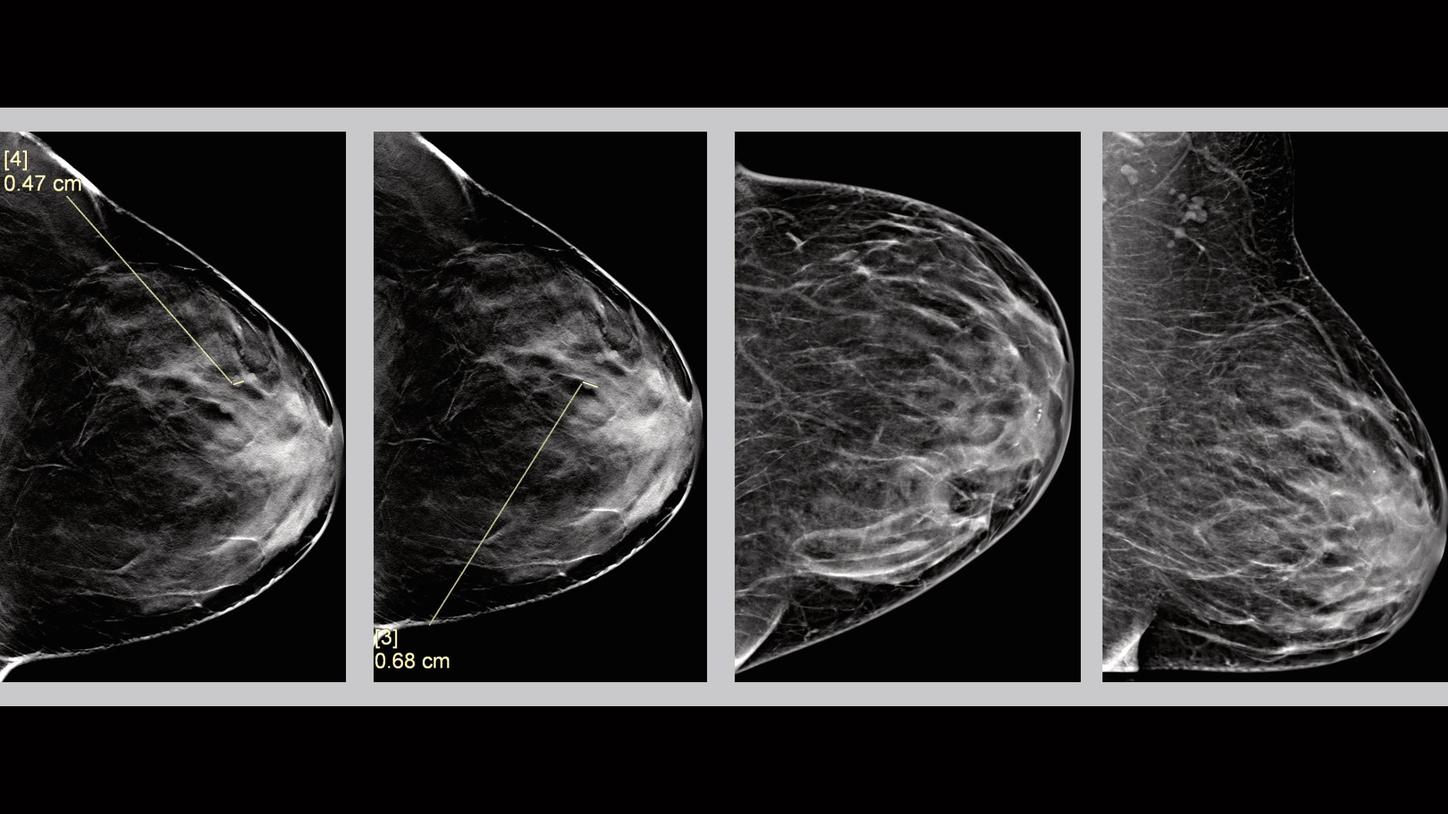

Clinical Evidence – Tomosynthesis - Case 3

History

Patient is 46 years old and is seen for screening mammography. No personal or family history of breast cancer or any other cancer.

Mammography Findings

Finding 1

There are three circumscribed equal density masses noted on tomosynthesis images, in the anterior aspect of the left breast, at the upper outer quadrant (2 o’clock position), about 4 cm from the nipple. They measured about 0.6 cm.

Impression

BIRADS Assessment Category 2: Benign finding